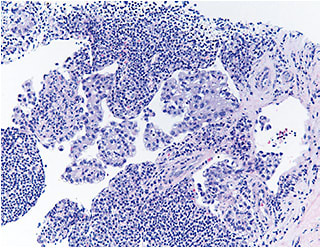

Pathology of an inguinal lymph biopsy was consistent with metastatic carcinoma with clear cell features of gynecological origin (Figure 5). Immunohistochemistry studies were positive for PAX8, a marker used to test for gynecological malignancies (Figure 6). Serum anti-enolase and anti-recoverin antibodies were positive, confirming the presence of paraneoplastic BDUMP as the cause of her recent eye findings.